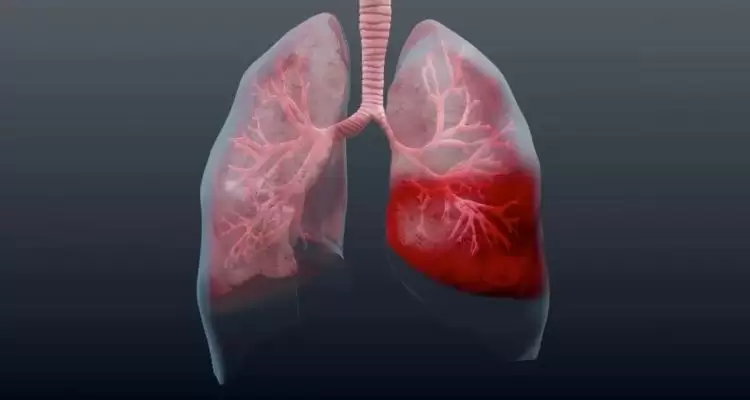

Такі ознаки говорять про серйозні порушення у верхніх дихальних шляхах, легенях або серцево‑судинній системі. Якщо негайно не звернутися за допомогою, можна померти.

- Рак легенів. Він, а також інші пухлини бронхолегеневої системи стають причиною кровохаркання в 20% кров в мокроті випадків.

- Тромбоемболія легеневих артерій. Так називають пошкодження легеневої тканини, яке відбувається через закупорку однієї з артерій тромбом.

- Важкі хвороби серцево-судинної системи. До них відносяться інфаркт міокарда, кардіоміопатії, пороки серця. При проблемах з серцем в легеневих кровоносних судинах різко підвищується тиск, що може викликати розрив судинних стінок.